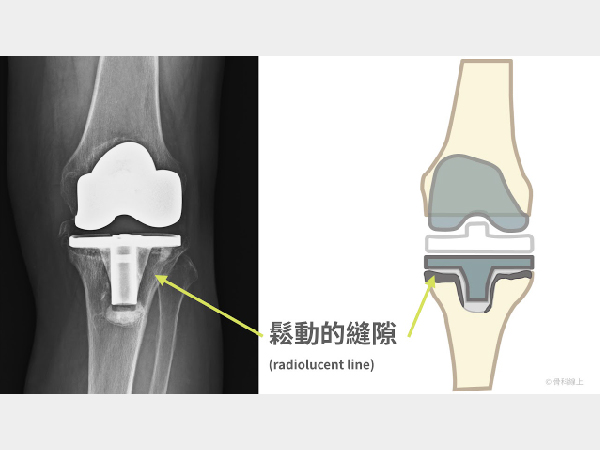

人工膝關節能用多久?談人工膝關節的失敗原因

2022-10-31

“所以醫生,我的人工膝關節能用多久?”“這個人工膝關節裝上去能用一輩子嗎?”要回答這個問題,讓我們先從人工膝關節可能有哪些失敗原因開始談起。